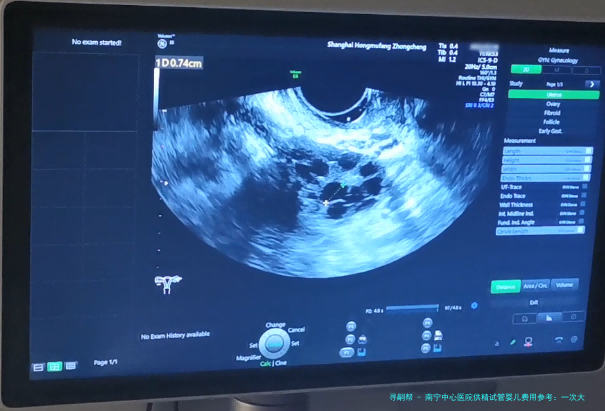

通过注射促排卵药物,刺激卵巢内多个卵泡发育成熟。 3.采卵手术:

在超声引导下,通过微穿刺方式取出成熟的卵子。 4.精子和卵子结合培育胚胎: